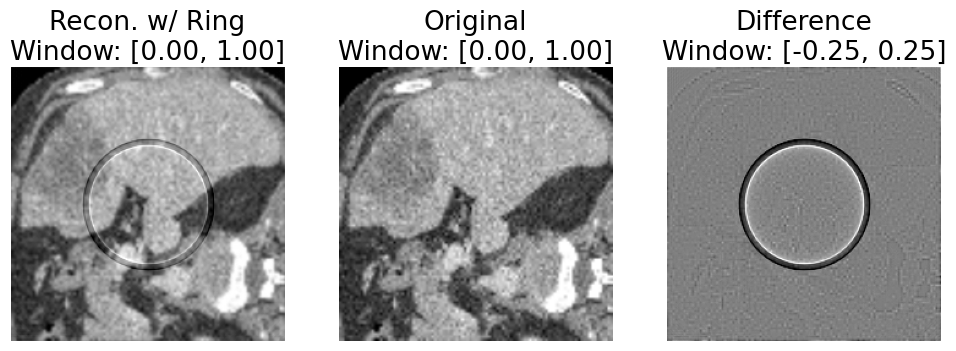

Refer to caption

Figure 3. Unintended reconstruction error mixed with intended simulated ring artifact (leftmost image is RdistortedR_{distorted}, middle image is OO, rightmost image is RdistortedOR_{distorted}-O). The error introduced by forward and backprojection makes it difficult to claim that RdistortedR_{distorted} represents the ring artifact in isolation, as RdistortedR_{distorted} can also be distinguished from the original image based on the error. For ease of visualization, we simulate 5 adjacent detector channels with gain error -10%.

We observe a notable “reconstruction error” introduced by our simulation approach. In particular, when considering discrete images, the result of performing forward projection followed by backprojection is not equivalent to the original image, as seen in Fig. 2. We were not able to mitigate this error by increasing the number of projection samples to increase the sampling resolution for the transform. We believe this may be a consequence of using relatively small images with far fewer samples than can be obtained with a real CT scanner and a physical volume. Unfortunately, with our approach, this unintended reconstruction error becomes mixed with the intentional simulated distortions we apply in sinogram space (Fig. 3), muddying the conclusions which can be drawn regarding domain adaptation.